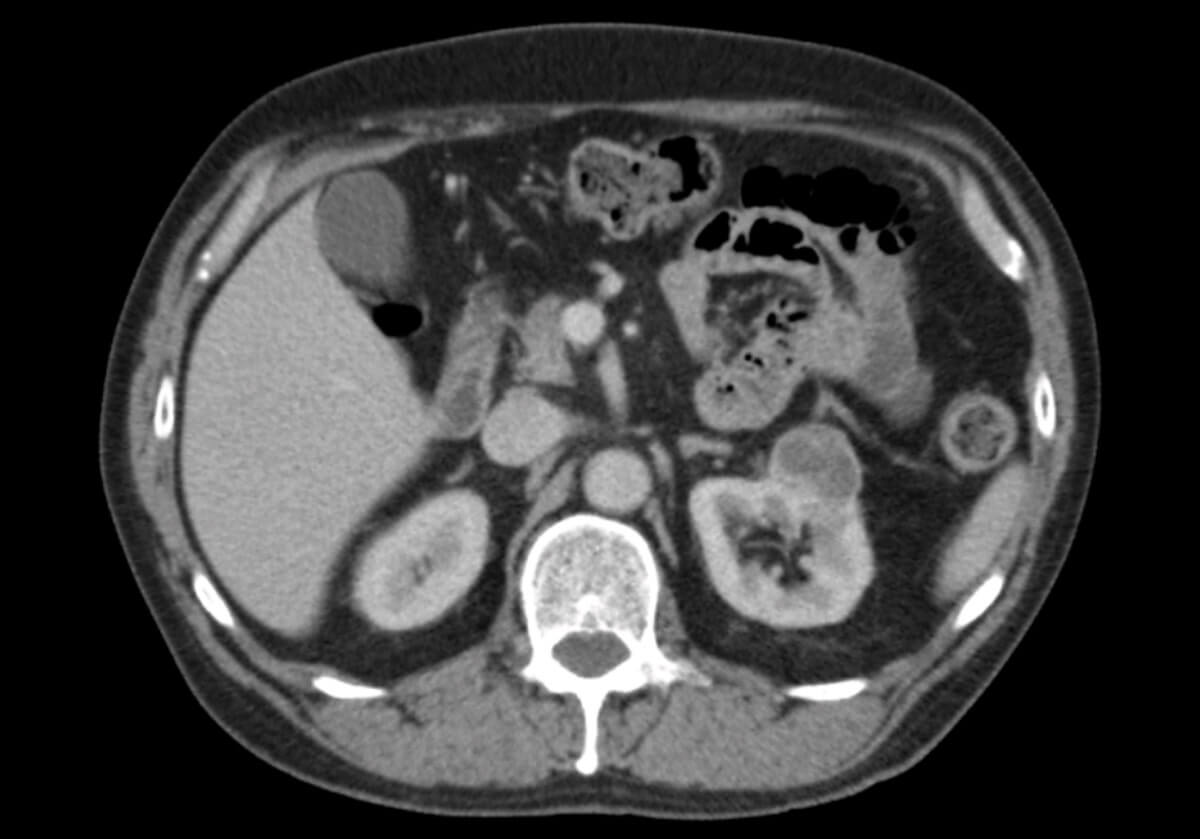

A 65-year-old gentleman was referred to our unit with a history of several months left upper quadrant pain and a CT scan demonstrating a 3.6cm enhancing cystic mass of the left kidney alongside a small left adrenal mass (Figure 1). He had a background of ischaemic heart disease, hypercholesterolemia, and hypertension.

Figure 1: An axial CT image demonstrating a 3.6cm cystic mass of the left kidney.